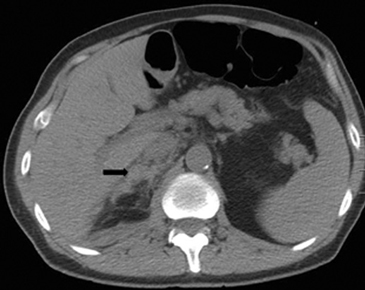

Tanto las lesiones benignas como malignas pueden presentar una atenuación heterogénea, especialmente en fases contrastadas, pero la presencia de grandes focos necróticos son mas bien orientadores de malignidad (Figura 8 a y b).

A

B

En TC sin contraste por lo general se observa una masa heterogénea, especialmente en caso de lesiones de mayor tamaño por la presencia de necrosis. Entre un 19 a 33% de los casos se identifican calcificaciones. Luego de la administración de contraste su refuerzo es heterogéneo y su patrón de lavado es consistente con una enfermedad maligna (Figura 22).